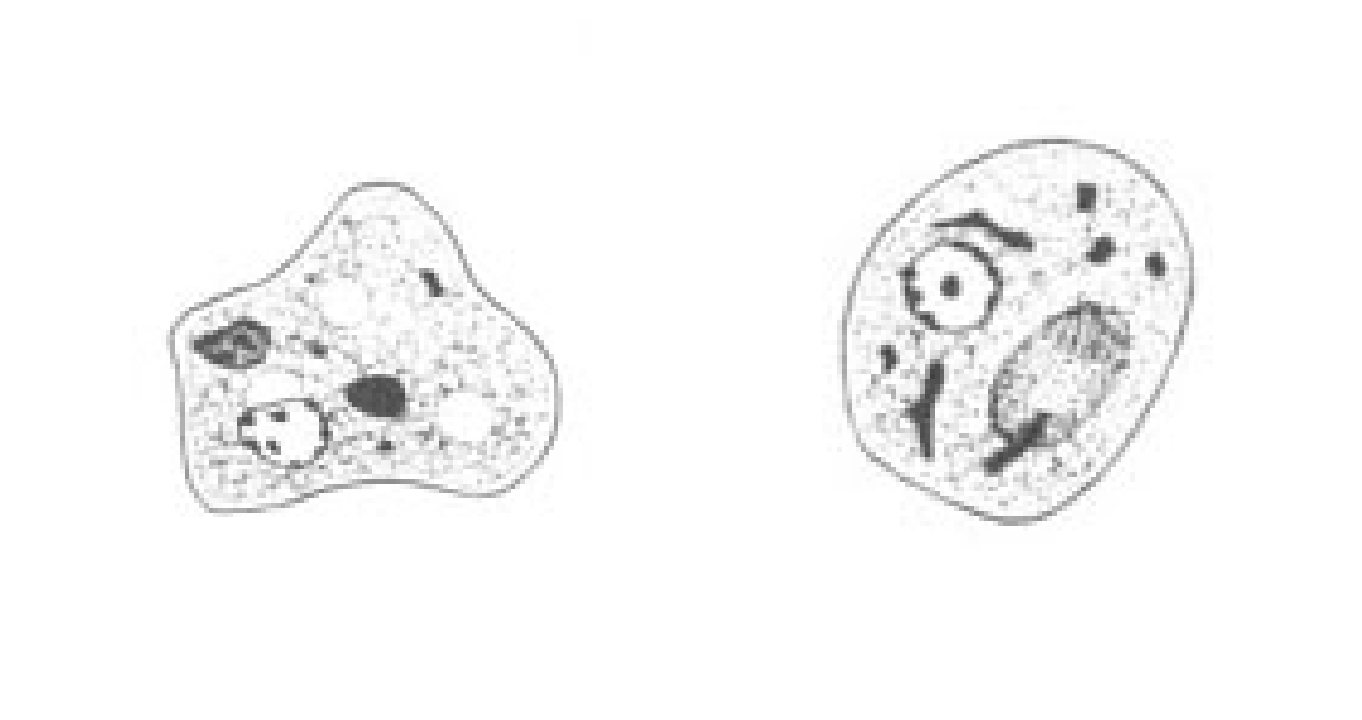

E. nana

E. nana troph form

E.nana troph form

What cyst form ameba is characteristically oval and has up to 4 nuclei?

E. nana

E. nana cyst

E. nana cyst